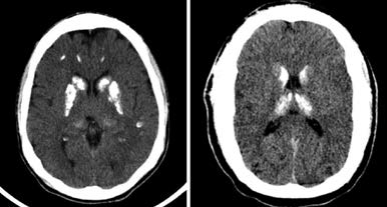

Tomografía de cráneo simple. Nota aclaratoria: se identifican múltiples calcificaciones ganglio-basales bilaterales comprometiendo el putamen, el núcleo caudado, los lóbulos frontales, los parietales, pero sin compromiso del cerebelo. El mesencéfalo, el sistema ventricular y el tallo estaban normales

Figura 3: Tomografía de cráneo simple. Nota aclaratoria: se identifican múltiples calcificaciones ganglio-basales bilaterales comprometiendo el putamen, el núcleo caudado, los lóbulos frontales, los parietales, pero sin compromiso del cerebelo. El mesencéfalo, el sistema ventricular y el tallo estaban normales

Fuente: elaboración propia